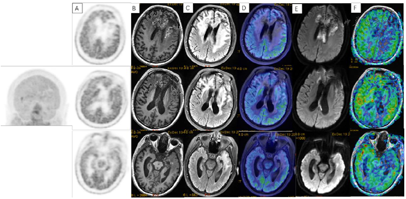

术后3周患者就诊于头颈肿瘤放化疗科,专科查体:左眼睑下垂,神清,言语清晰,伸舌居中,双侧瞳孔等大等圆,对光反射存在,四肢感觉活动可,肌力肌张力正常。2017年7月MR(图4)示左额叶术后改变伴出血,病灶内侧部分考虑肿瘤残留可能。为了更好地评估术后残留病变范围和制定放疗计划,患者行11C-MET PET/CT检查(图5A-D),结果示左侧脑室前角旁-左侧基底节区团块状稍高密度影,蛋氨酸代谢异常增高,考虑肿瘤残留。参照2016 ESTRO-ACROP指南[1],继发性胶质母细胞瘤放疗GTV靶区需包含术腔、T1增强上的强化区域及T2 FLAIR上的高信号区域,术后PET/CT显像所示的氨基酸代谢活跃病灶被包含在GTV之内(图5E)。患者于2017年7月始行左额叶病灶放疗(PTV 60Gy/30F,同步口服替莫唑胺化疗75mg/m2,qd)。结束后复查PET/CT(图5F-I)示病变范围明显缩小,代谢程度较前减低,左额叶少许病变存活,遂对残留病灶局部放疗加量(GTV如图5J,6Gy/3F)。放疗过程顺利,期间出现Ⅲ°白细胞减低,予以升白细胞治疗后好转出院。后于2017年10月起口服替莫唑胺辅助化疗(150~200mg/m2,d1-d5,q28d),期间规律复查。